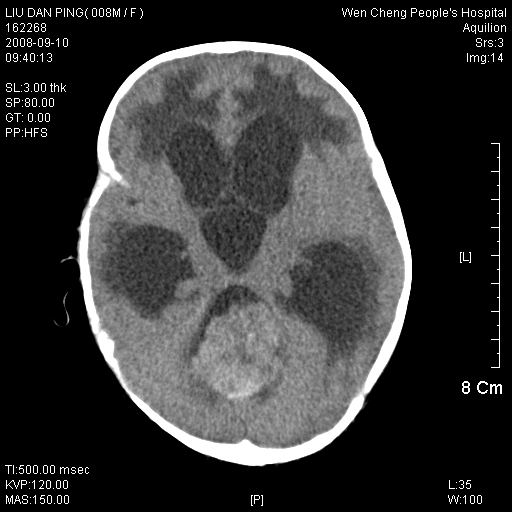

以下是引用深泽交通医院在2008-9-10 15:08:00的发言:[br]髓母瘤并脑积水

以下是引用卜一在2008-9-10 16:21:00的发言:[br]髓母细胞瘤伴梗阻性脑积水!支持![br]髓母细胞瘤特点:—般直径大于3.5cm,位于后颅凹中线之小脑蚓部。累及上蚓部的肿瘤延伸到小脑幕切迹之上,ct平扫肿瘤多呈均匀一致的高或等密度病灶,增强检查呈均匀一致的强化。病灶中有小坏死时,平扫亦可呈不均匀之混杂密度,注药后有增强。[br]

以下是引用yuhongjun在2008-9-10 16:57:00的发言:[br]髓母细胞瘤伴梗阻性脑积水.

以下是引用zjzjr在2008-9-10 15:09:00的发言:[br]髓母细胞瘤伴梗阻性脑积水.